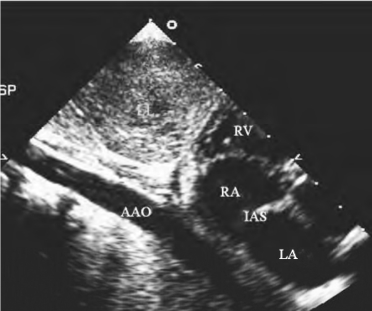

-